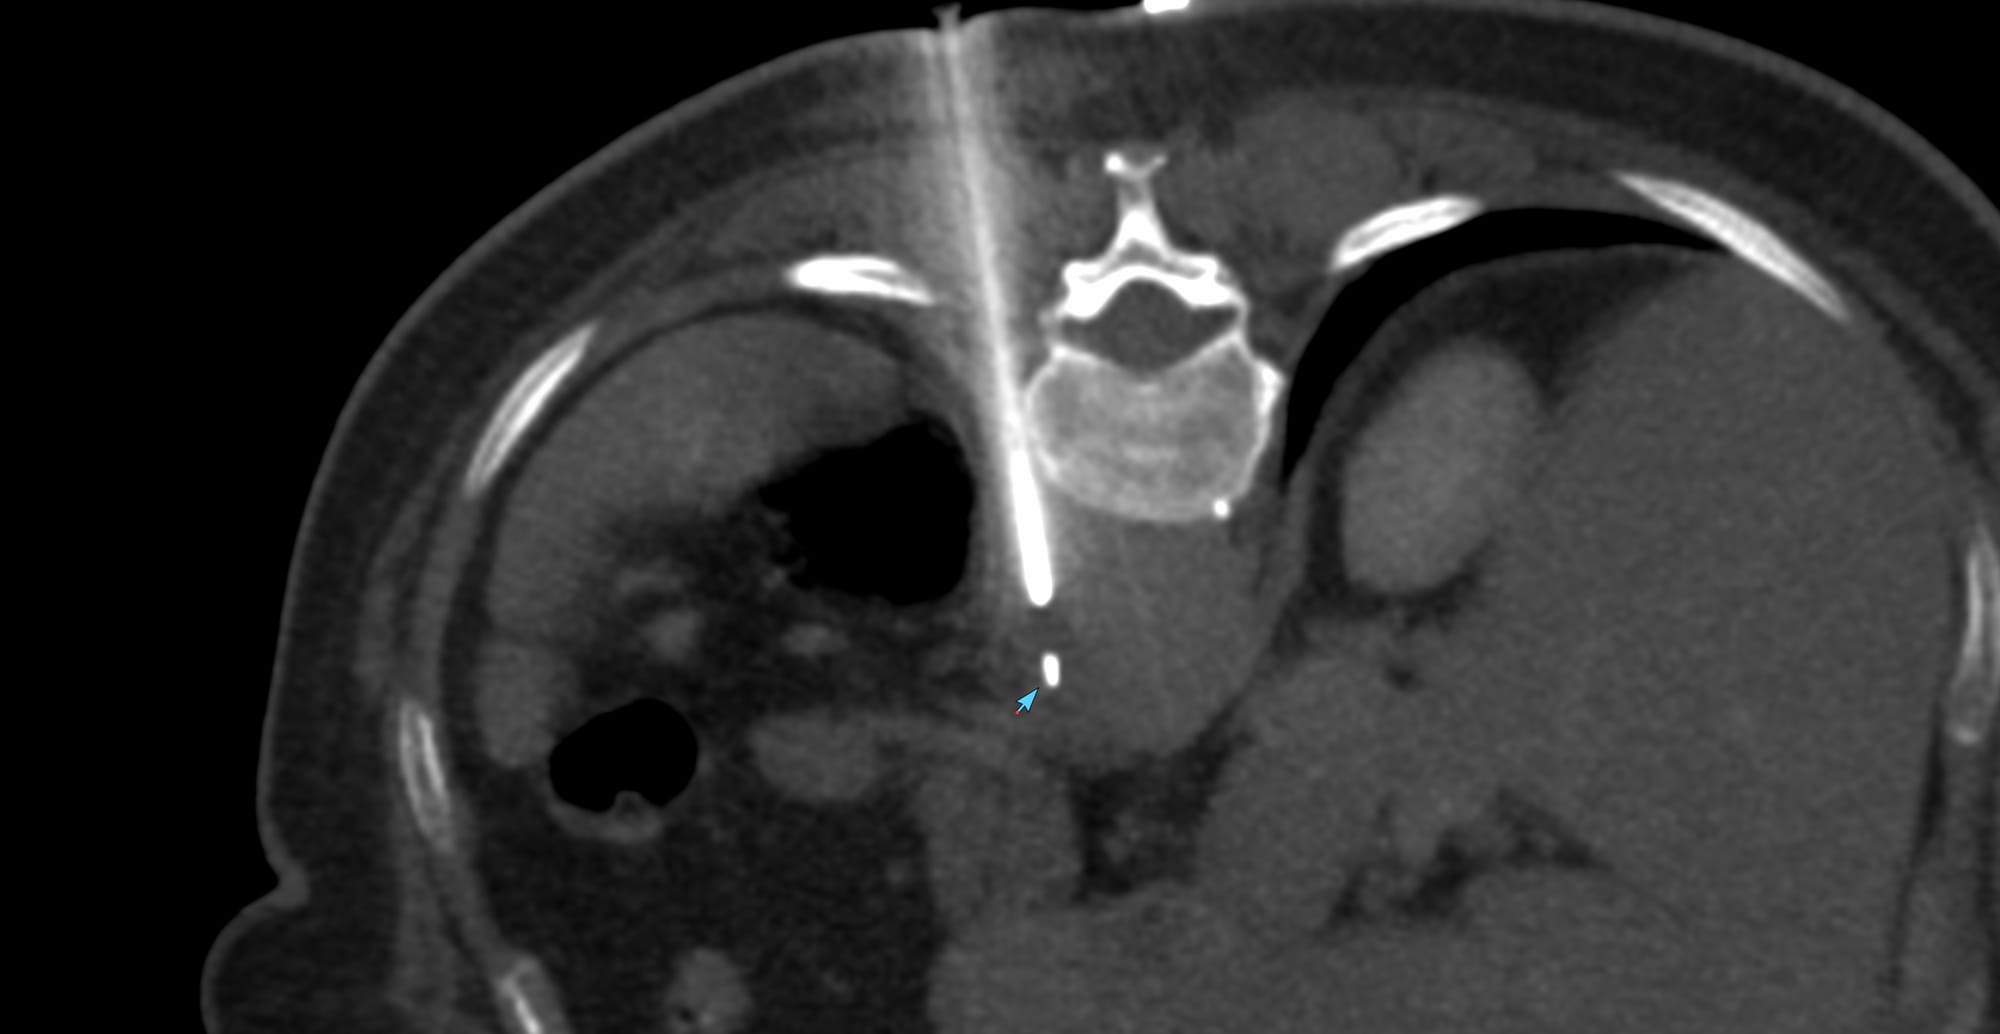

Case 170 - Peri-Aortic Soft Tissue Biopsy

Bhavin Jankharia - 23 August 2025